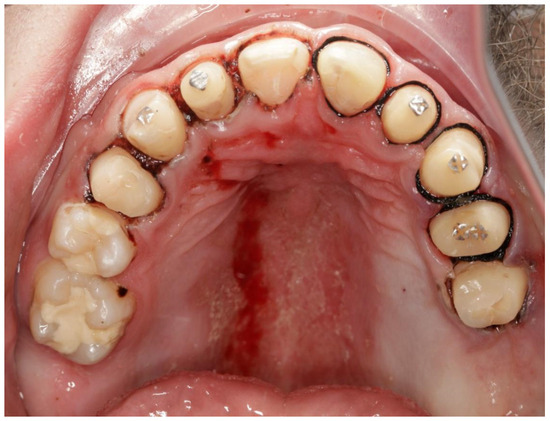

Use of Computer Digital Techniques and Modern Materials in Dental Technology in Restoration: A Caries-Damaged Smile in a Teenage Patient

2. Case Report